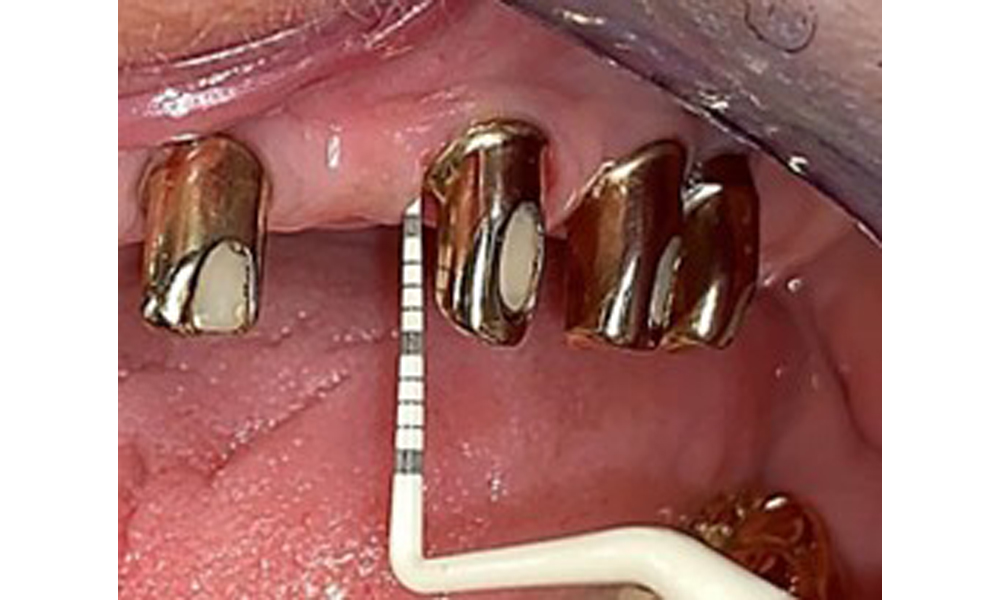

The patient was fitted with a combined removable maxillary telescopic prosthesis more than 25 years ago (Fig. 1, Fig. 2, Fig. 3) and is very happy with her dentures. The patient has an adequate fixed denture for the mandible (Fig. 4).

The dental findings are as follows: Combined removable implant and tooth-supported telescopic prostheses on implants 15, 13, 21, 23, 24, 25 and tooth 11 (Fig. 1, Fig. 2, Fig. 3). The patient was fitted with a fixed mandibular denture. Adequate bridges were present over 37 to 34 and 45 to 47 (Fig. 4), the crown margins were intact and there were no active caries. A composite filling with a marginal gap was present on tooth 43. There was mandibular gingival recession, exposing 1 to 3 mm of root surface. This also applies to 11.